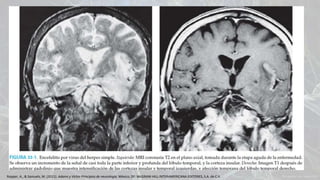

IMAGEN

• Rx de tórax  neumonía o absceso

• TAC: puede mostrar la presencia de un

absceso o empiema subdural

• Dilatación meníngea y de los ventrículos

• Edema cerebral

• Infarto cerebral

• RM con gadolinio: exudado meníngeo y

la reacción cortical

Diagnostico

Corte sagital donde se aprecia una acentuación

brillante de las meninges.

Indicaciones de estudios de imagen antes

de la punción lumbar:

• Edad mayor de 60 años

• Crisis convulsivas en los 7 días

previos

• Inmunocompromiso

• Historia de patología de SNC

• Alteración del estado de alerta

• Datos de focalización

• No se debe retrasar la antibioterapia